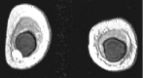

Left images show intracapsular rupture in the left implant ("linguini sign").   Right images from a contrast dynamic scan show an intensely enhancing mass adjacent to a right implant.

High-resolution MRI is extremely accurate for diagnosing silicone and saline implant rupture.   The so-called "linguini sign" refers to serpiginous thin lines seen with intracapsular rupture (left 3 images above).   Various new "silicone techniques" can also detect extracapsular extravasation of silicone.

MRI is utilized in patients with dense breasts and indeterminate masses who have a non-diagnostic x-ray mammogram and ultrasound.   MRI is only an adjunct technique.   If a mass is suspected, a contrast-enhanced dynamic study is performed with IV Gadolinium.   This is usually done with high-resolution (1-2 mm) coronal sections pre and post rapid infusion of contrast (using an MR-compatible power injector) in a dynamic fashion (usually 4 or 5 post contrast sequences are obtained as shown in top right 3 images).   Contrast uptake graphs of suspicious masses are obtained.   Malignancies tend to take up contrast more rapidly.